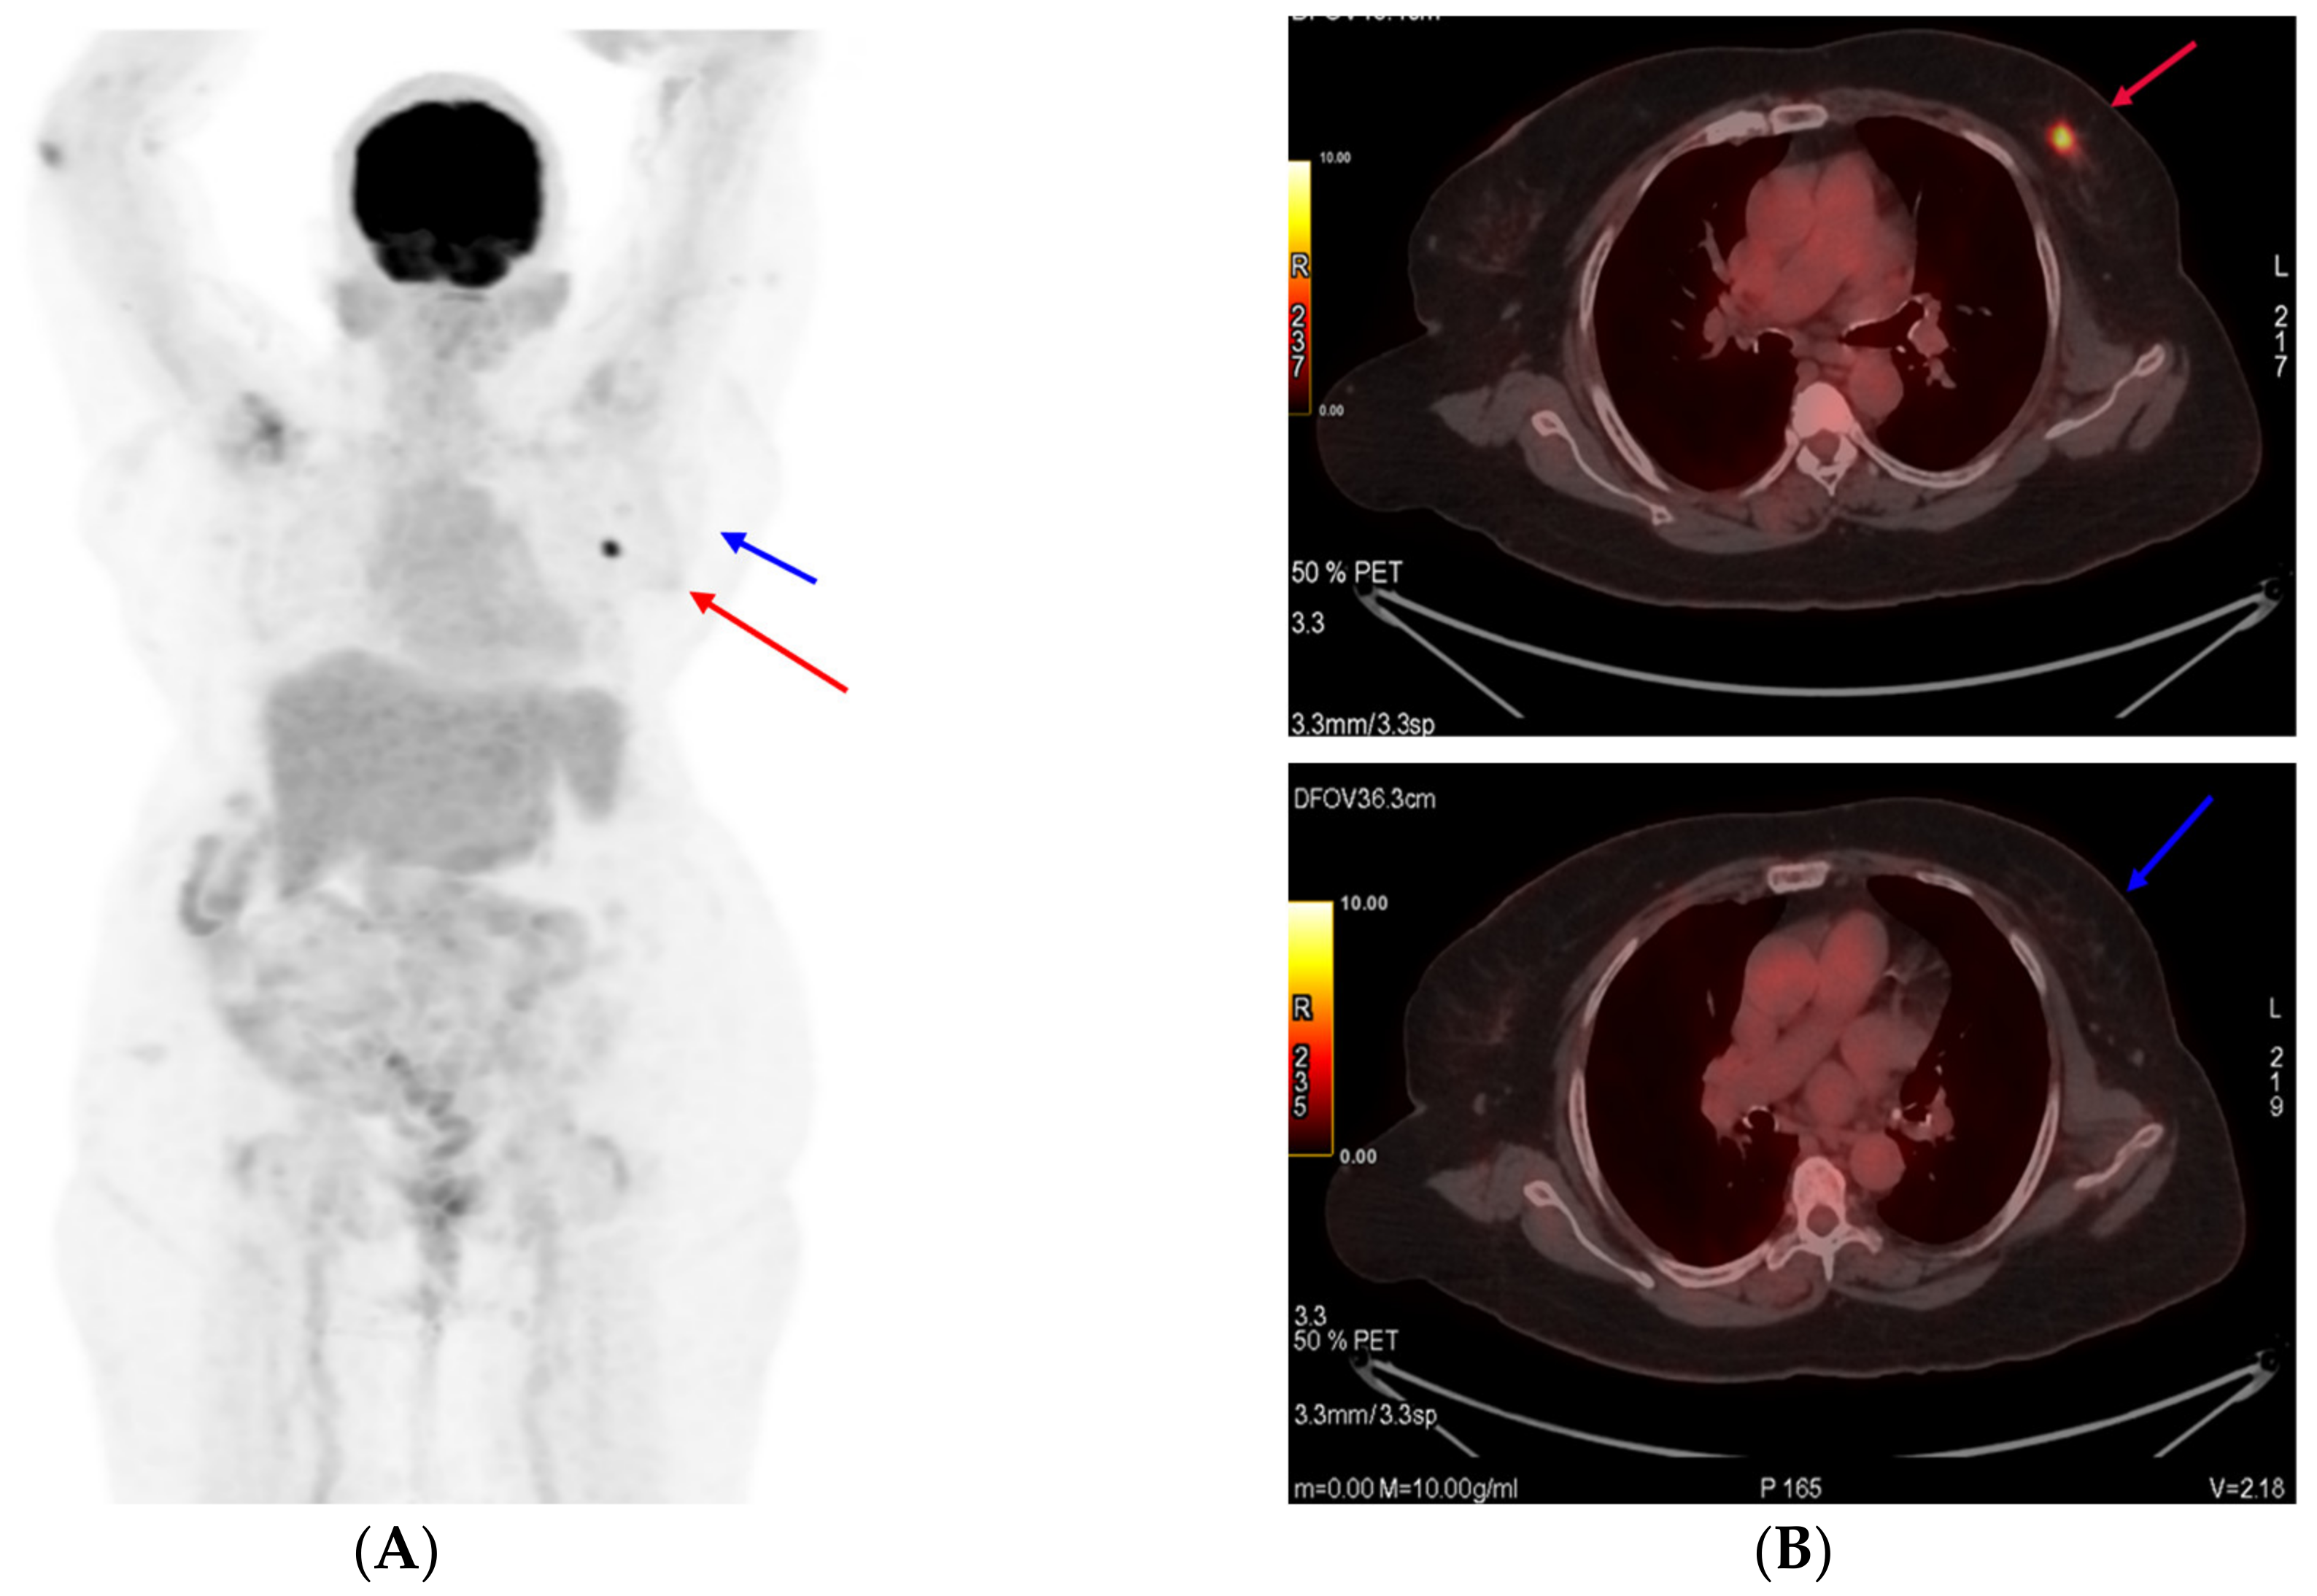

A response evaluation via a PET CT scan showed a significant decrease in the size and metabolic activity of the primary left breast lesion, along with regression and metabolic resolution of the left level-I axillary nodes in the patient (partial response, PR, by RECIST 1.1). The patient underwent surgery, namely modified radical mastectomy. A post-operative histopathological examination was suggestive of residual disease with invasive ductal carcinoma, grade: II, tumor size: 1.2 cm, lymph nodes: 1/25, and ypT1cN1aMx. In view of pathological complete response not being achieved, it was decided to continue T-DM1 and complete one year of anti-HER2 therapy. The patient completed one year of T-DM1 therapy with no adverse events. A PET CT scan was performed in May 2022 and showed no evidence of metabolically active disease (Figure 4). She had completed twelve total cycles of T-DM1 and opted to continue with endocrine therapy. She was subsequently initiated on endocrine therapy and continued dialysis. In order to publish this report, written informed consent was obtained from the patient and her legal guardian for the disclosure of images and clinical details.

Figure 4.

Post-treatment PET scan images. No evidence of the tumor is seen (target 1), shown as a red arrow, and lymph node (target 2) shown as a blue arrow.